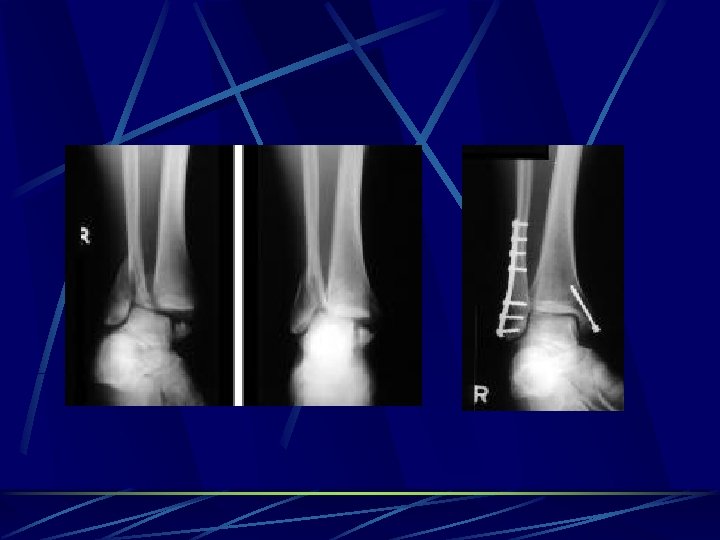

Spetial types of osteosynthesis LISS ( less invasive stabilisation system) implants for MIPPO (minimal invasive percutane plate osteosynthesis) -Herbert´s screw – scafoid # DHS – NOF# basicervical PFN – NOF # pertrochanteric Phillos –prox. humerus DCS (dinamic condylar screw) and DFN (distal femoral nail) - dist. femur Pilon plate – dist. tibia